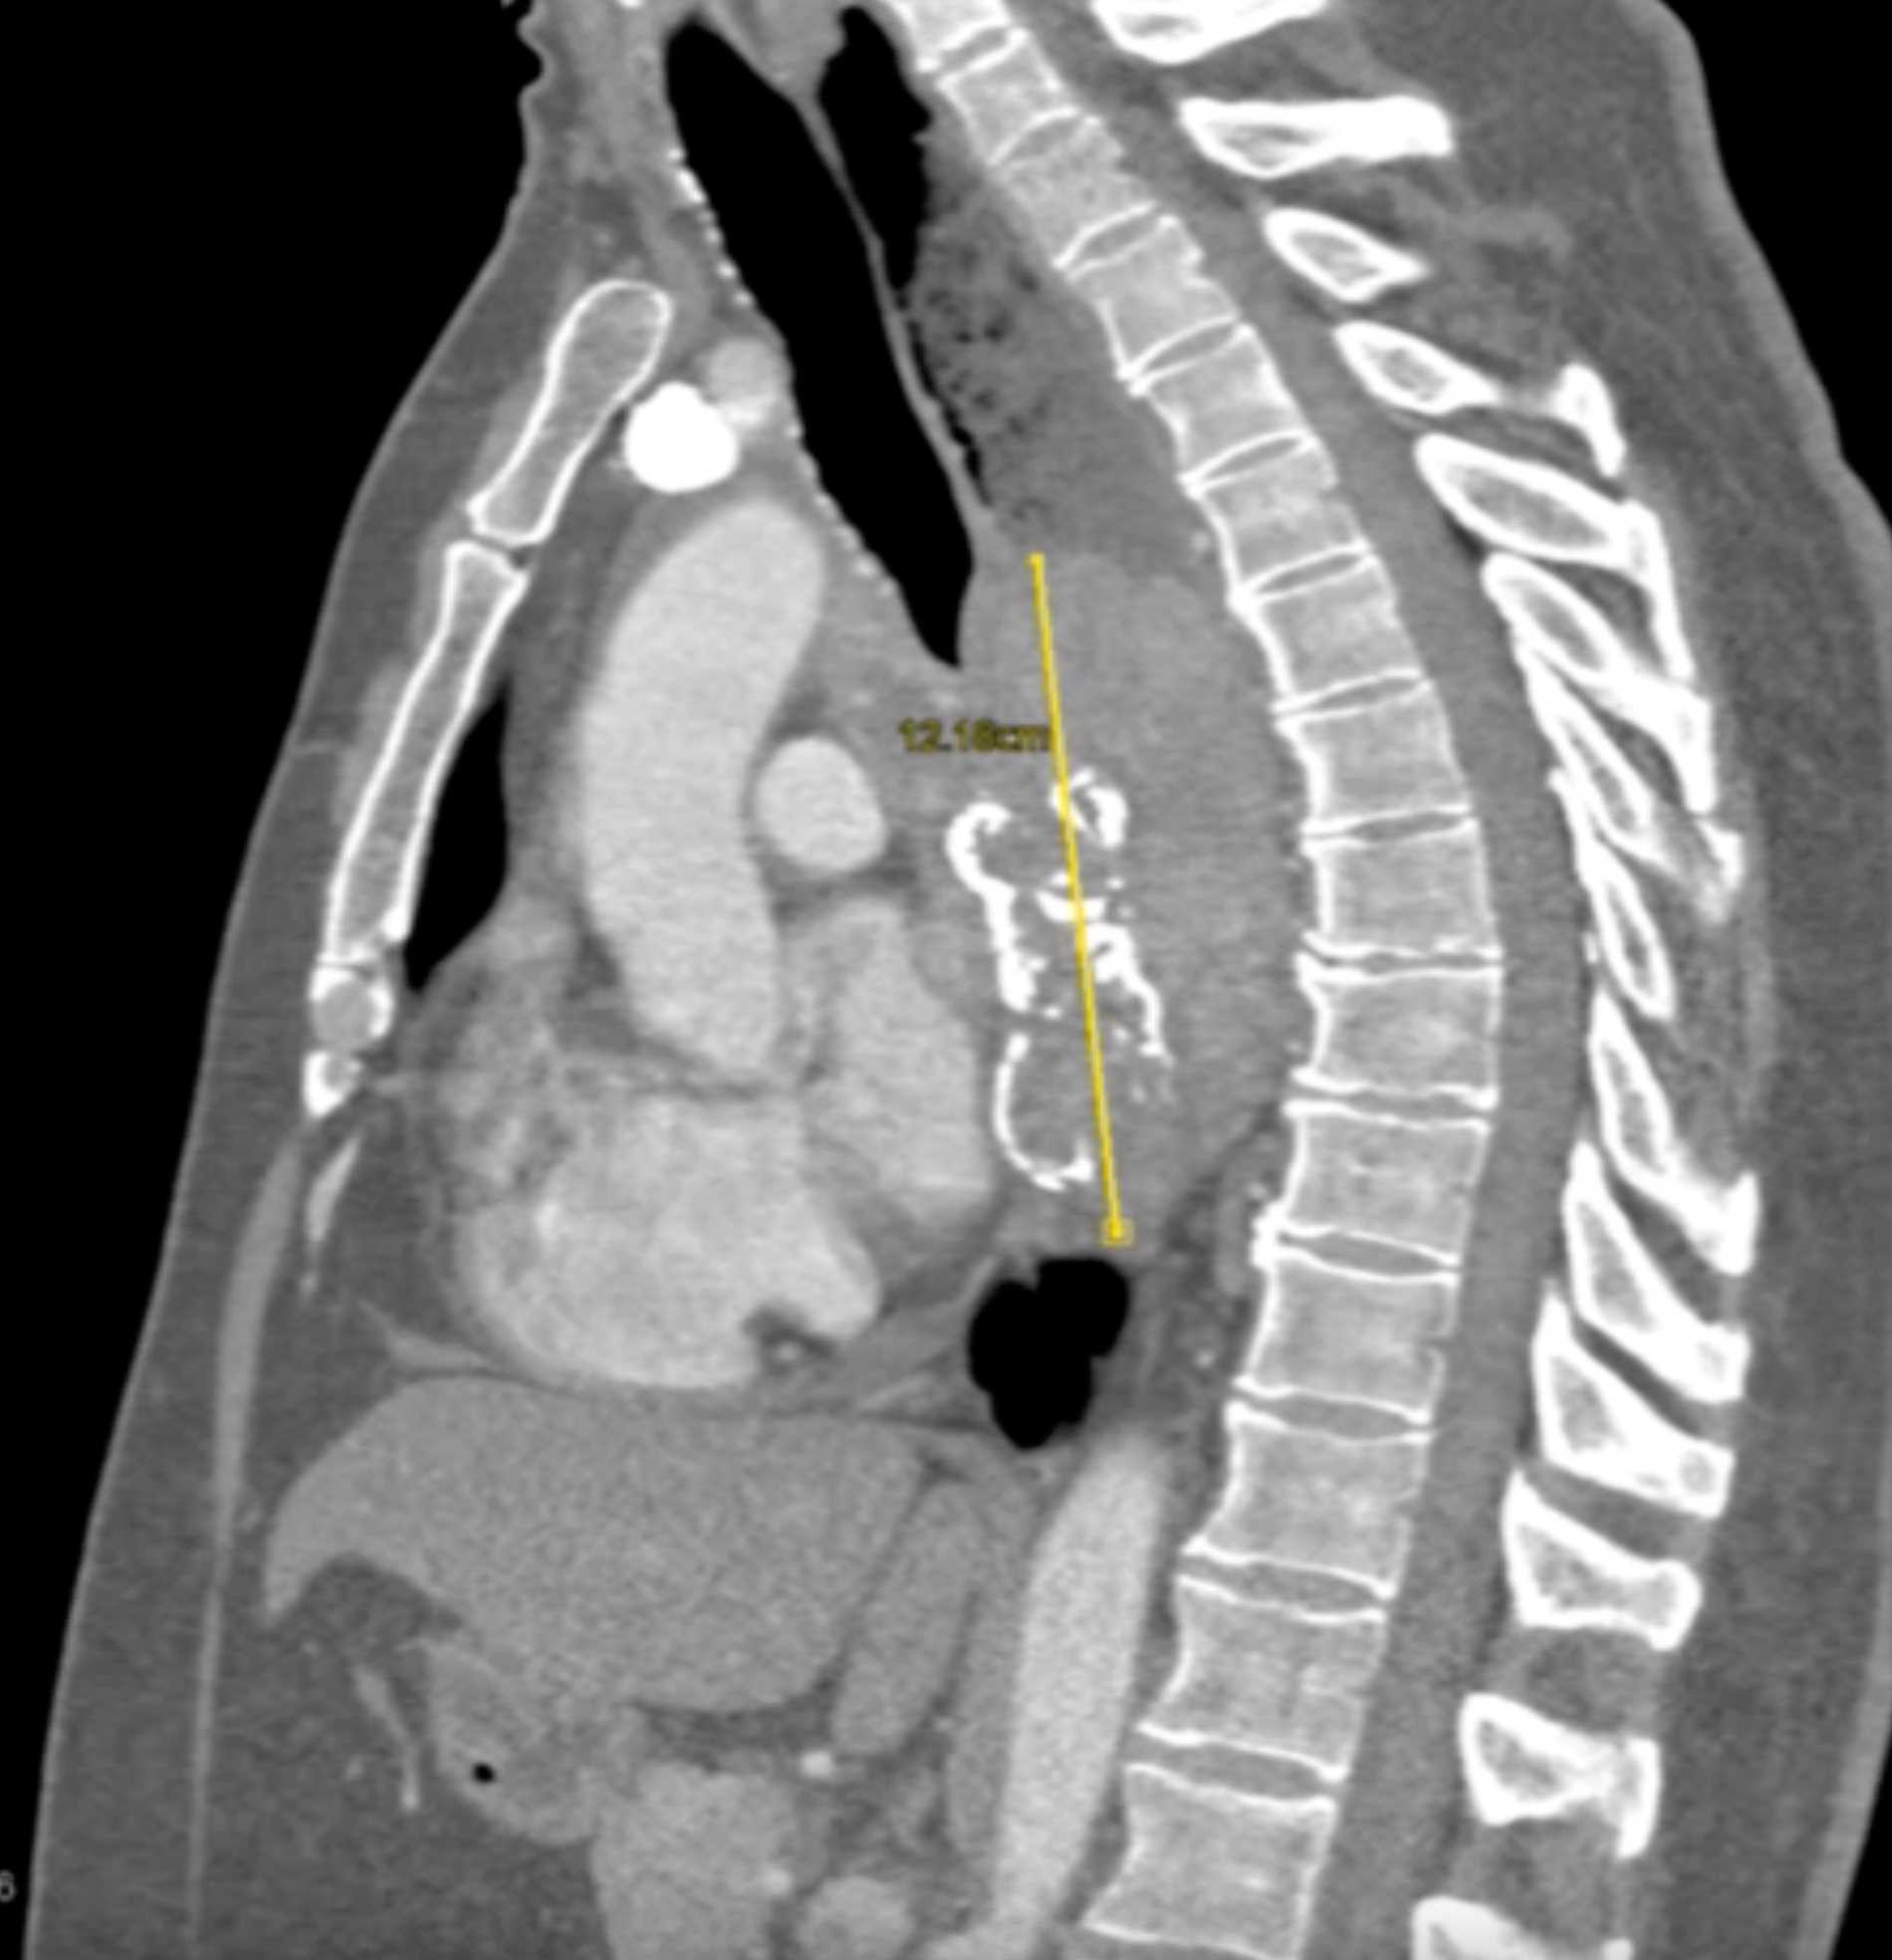

Fibrosing Mediastinitis